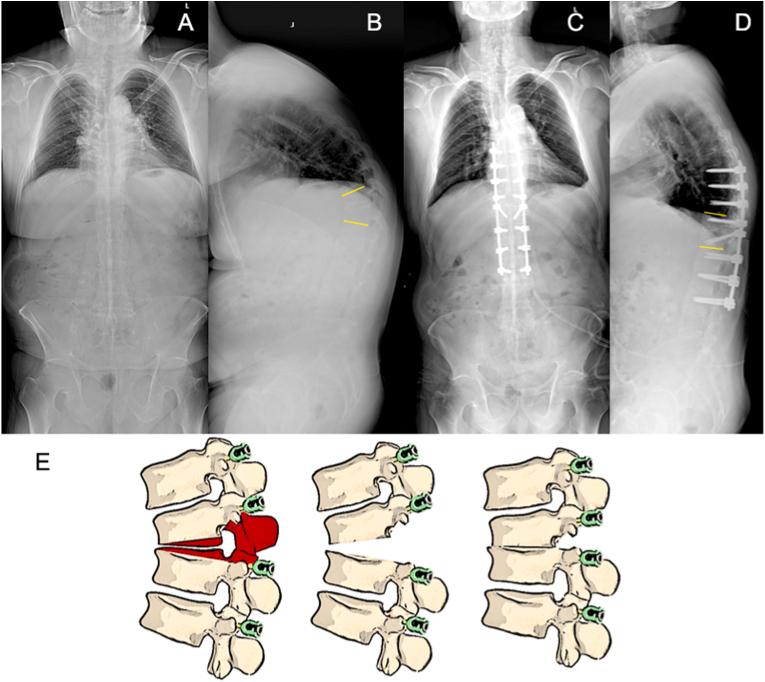

经椎间间隙后路脊柱矫正截骨手术的经椎间截骨分类

Trans-intervertebral osteotomy classification of posterior spinal corrective osteotomy procedures via the intervertebral space.

•This is a diagnostic study for a classification for posterior spinal osteotomy procedures via the intervertebral space.•Proposed ​ ​with ​ ​and ​, differ from the SRS-Schwab osteotomy classification.•Give of "" () for posterior spinal osteotomy procedures.•Thoroughly discussed about the of posterior spinal osteotomy procedures via the intervertebral space.•Systematically introduced the TIO technique with .

摘要

•这是一项关于经椎间隙后路脊柱截骨手术分类的诊断性研究。

•与SRS - 施瓦布截骨分类法不同,由[具体人员1]和[具体人员2]提出。

•给出了后路脊柱截骨手术的“[具体名称]”([具体描述])。

•深入讨论了经椎间隙后路脊柱截骨手术的[相关内容]。

•系统介绍了采用[具体技术]的TIO技术。